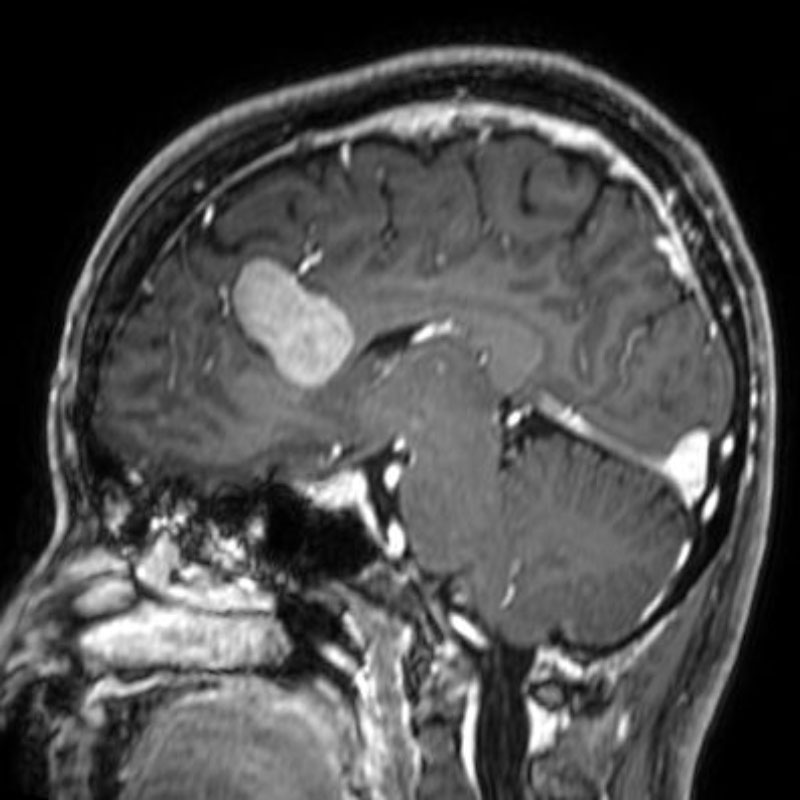

No.’25_108 手術前1

No.’25_108 手術前2